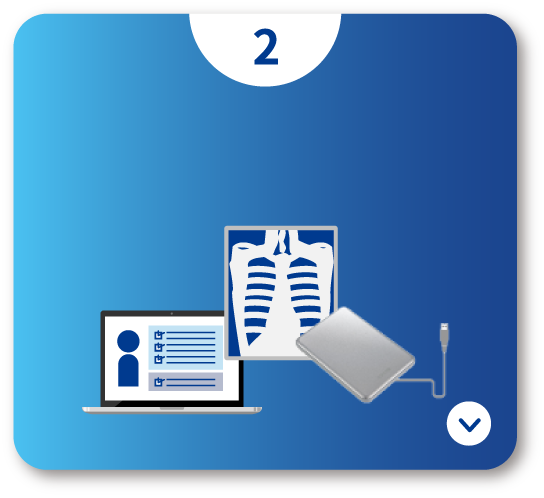

外部読影も簡単にシステム化したい!

- セキュリティ機能付きのメディアを使い、外部でもレポート入力可能

- ネットワークも事前のソフトウェアインストールも不要!手軽に読影開始

- メディアからビューア&レポートが起動し、自宅や勤務先のPCで所見入力

- ネットワーク環境下では、オンラインでのデータ授受も可能

オフラインレポート

データ+システム

(セキュリティ機能付き)

急な医師の交代や、環境の変化にも簡単に対応可能。

外部に多く読影依頼している施設は必見です!